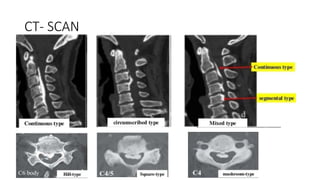

Types of OPLL

CT- SCAN

• #19 S 39 % M 29 Con 27 Circ 5 Investigation committee on OPLL of Japanese ministry of pubic health and welfare

• #20 Circumscribed : lesion located post to disc space Segmental : post to vertebral body Continous : several vertebral bodies